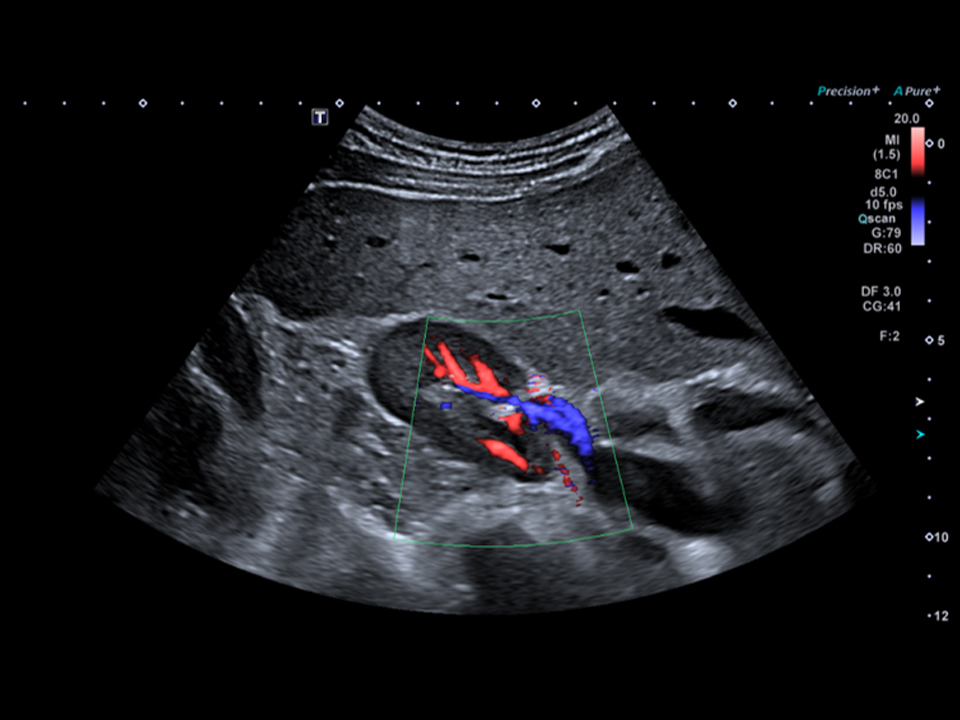

SMI – Superb Micro-Vascular Imaging – nowa innowacyjna technika dopplerowska Canon pozwalająca pokazać najmniejsze naczynia

bez artefaktów ruchowych. Najnowsze algorytmy pozwalają wyizolować i wyciąć artefakty powstające od ruchu otaczających naczynia tkanek zachowując informację o mikroskopijnych przepływach, które były usuwane przy pracy ze zwykłym Dopplerem kolorowym.

Zastosowanie SMI pozwala z dużo większą dokładnością ocenić niezwykle niskie przepływy, takie jak w korze nerek, w węzłach chłonnych, guzach oraz w przypadku neowaskularyzacji i niedokrwieniu.

- wyjątkową czułość i rozdzielczość przy niskich prędkościach przepływu

- wysoka ilość klatek w trybie kolorowym i monochromatycznym

- ograniczenie artefaktów ruchowym

SMI jest dostępne w 2 trybach: monochromatyczny (skala szarości) i kolorowym.

- Tryb kolorów pokazuje jednocześnie informacje o otaczających tkankach jak i kolorowy przepływ w mikronaczyniach

- Tryb w skali szarości skupia się tylko na poprawie czułości i bardzo dokładnym pokazaniu unaczynienia, dzięki eliminacji tła z badanych naczyń.

Color Doppler Right Kidney